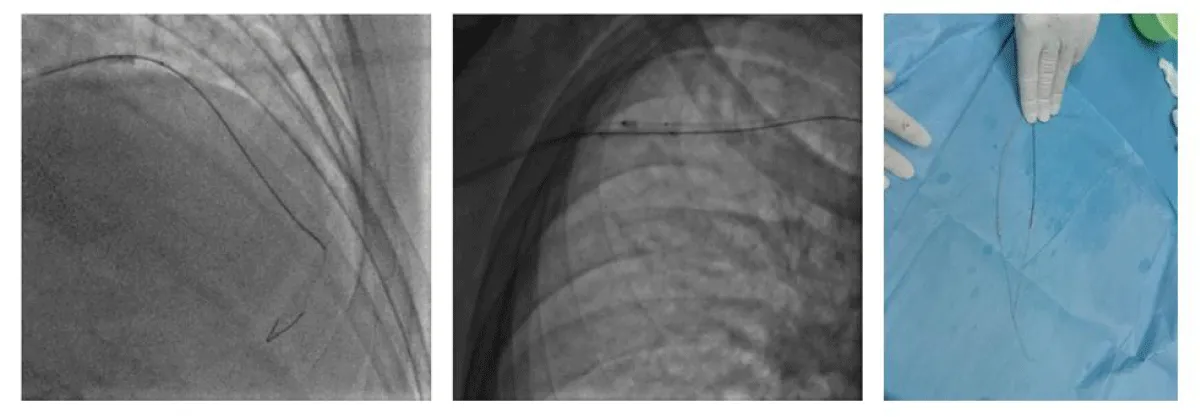

We started the procedure under 5000 UI of Heparin with an Extra Backup (EBU) 3.5 6 F guiding-catheter, we crossed the lesion with a floppy guidewire, however after dilatation with an NC balloon 2.5 × 12 the latter refuses to deflate and remains trapped in the lesion with the appearance of pain and an ST segment-elevation despite several attempts to dilute the product in the inflator and to burst it by overexpansion (Figure 2).

Figure 2: PCI and balloon trapping.

A traction on the balloon resulted in the deep intubation of the guiding-catheter which comes in contact with the trapped balloon and the rupture of the latter’s hypotube, which remains inflated at the site of the lesion partially in contact with the guiding-catheter and mounted on the 0.014 guidewire (Figure 3).

Figure 3: Rupture of the hypotube and guiding catheter deep intubation.

We put the second 0.014 guidewire distally in the LAD and twisted it with the distal part of the first guidewire, then we introduced a second balloon 2.0 × 20 over the second guidewire until the distal part of the guiding-catheter and inflated it between the guiding-catheter and the lesion to trap the stucked balloon between the second balloon and the guiding-catheter and to modify the lesion (to create a Cage and Buddy-balloon) (Figure 4).

Figure 4: Cage and Buddy-balloon./p>